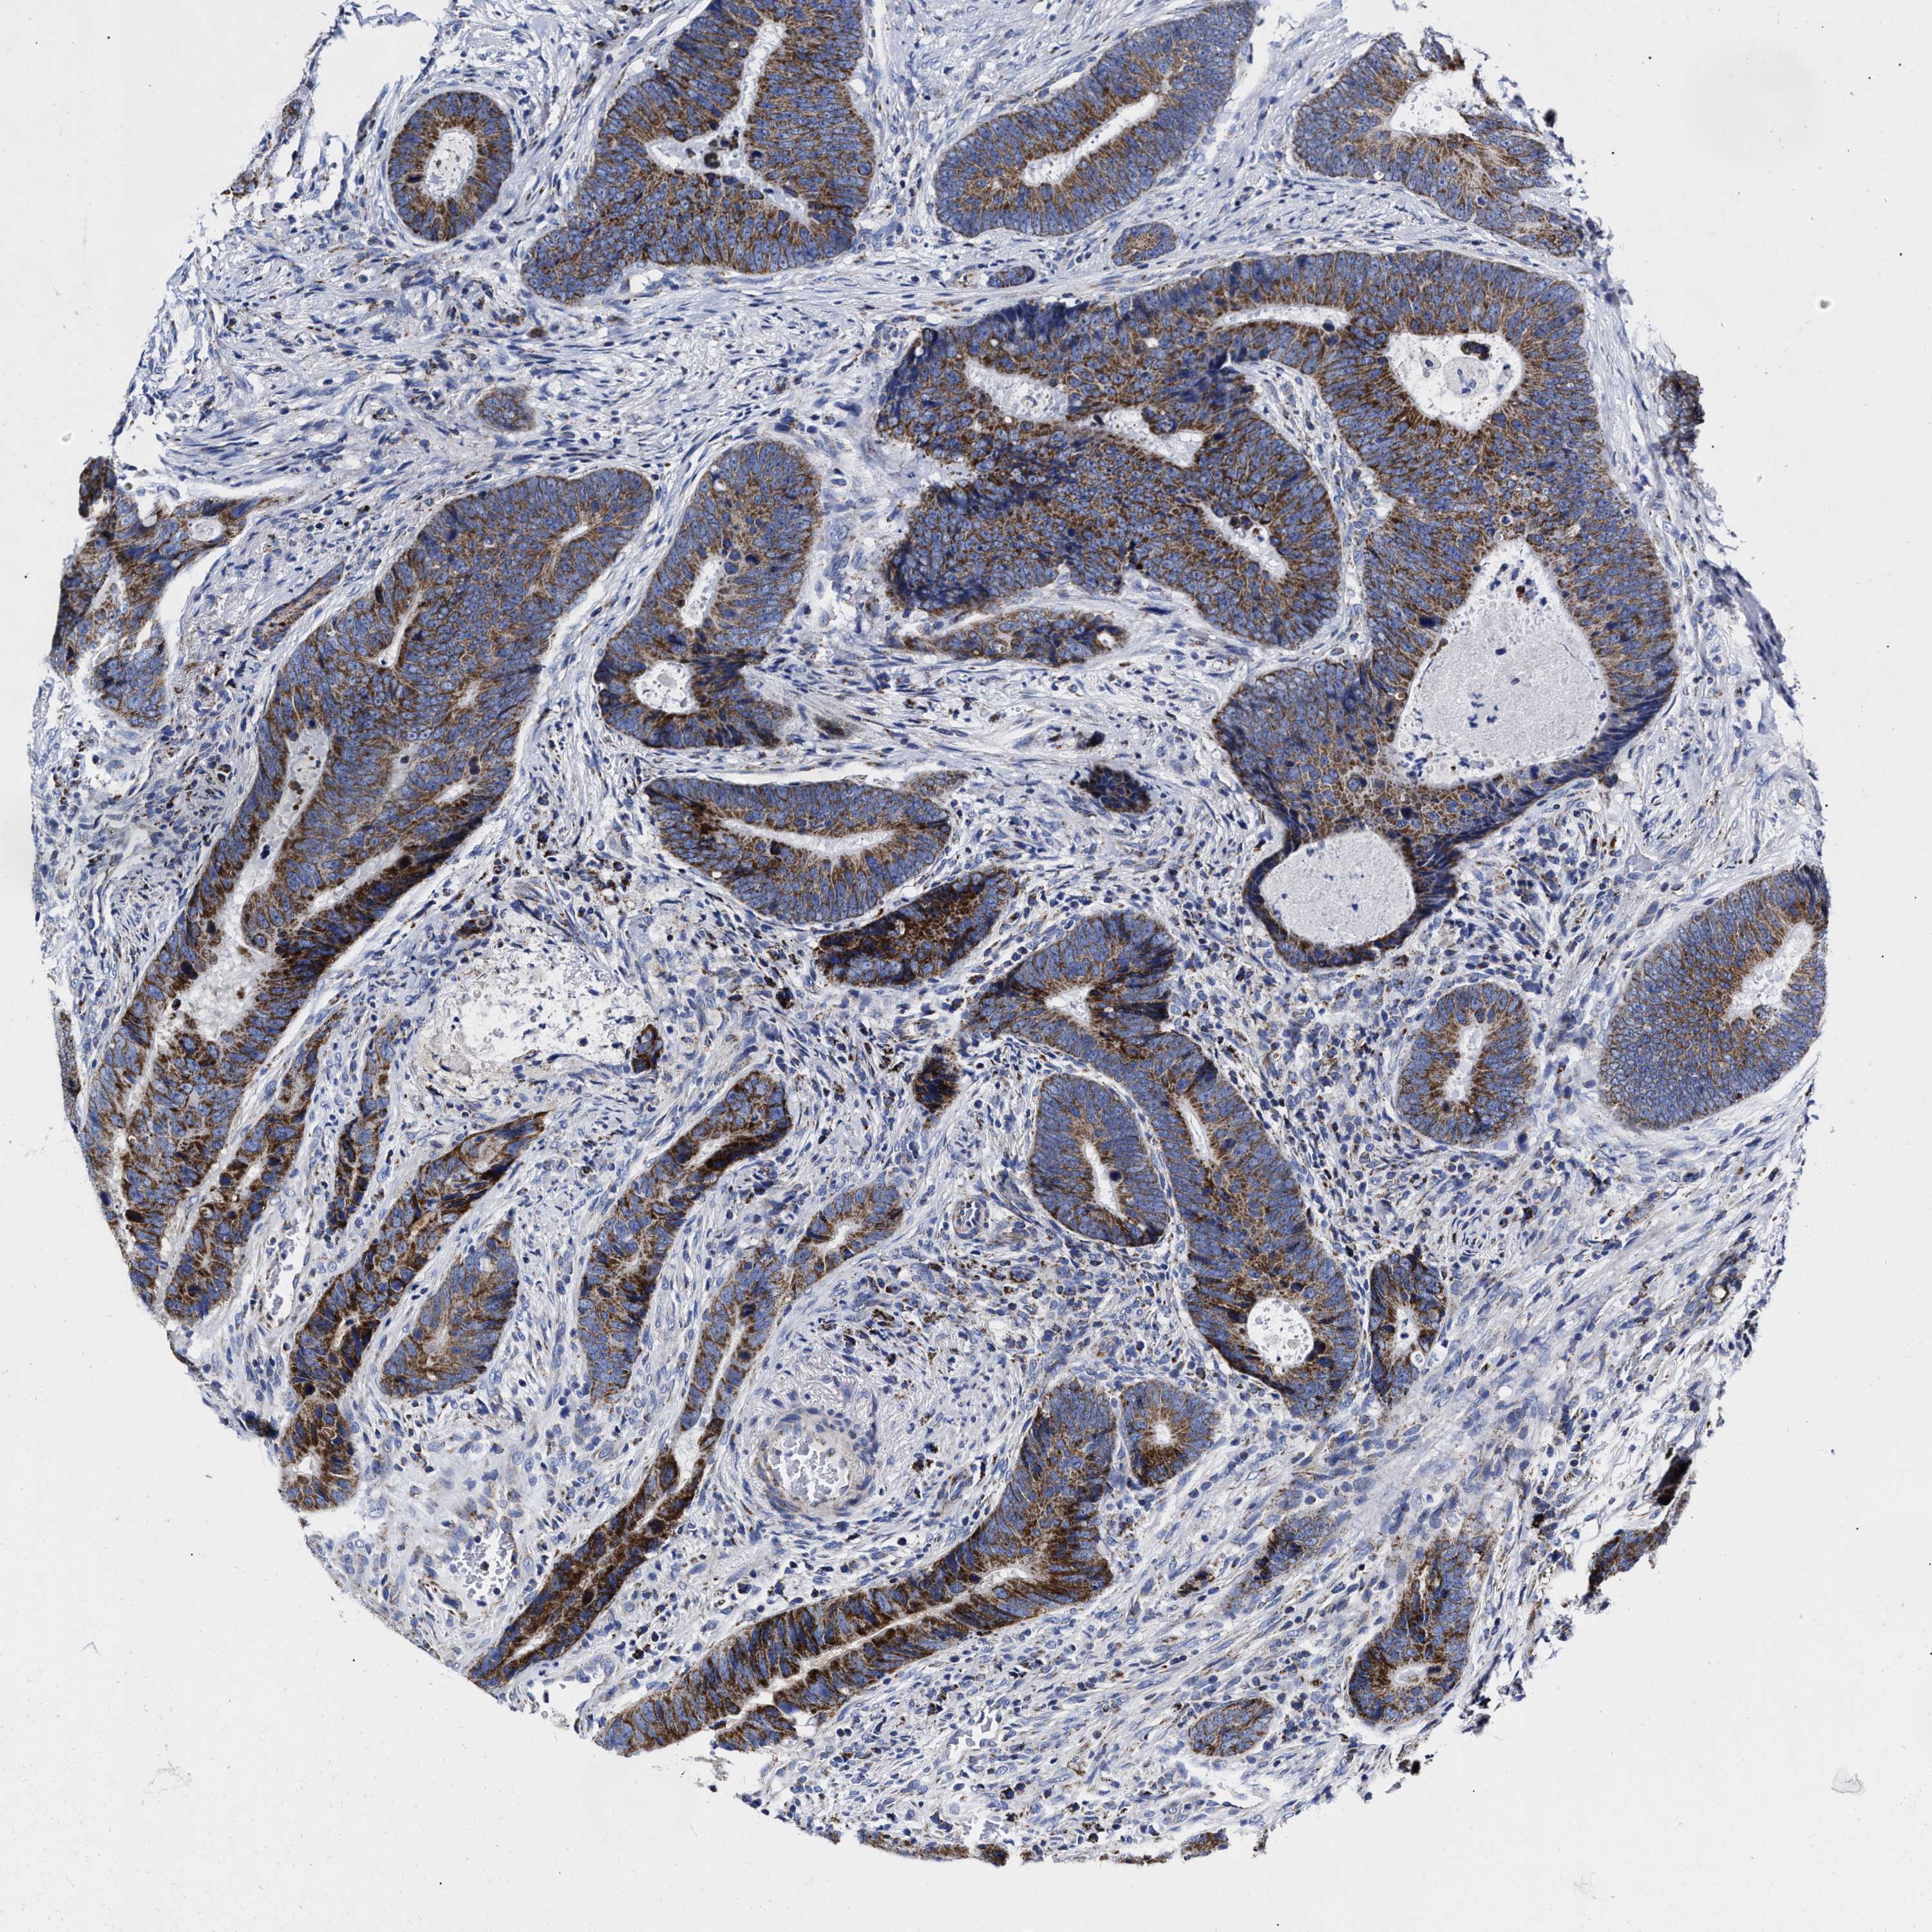

CANCER COLORECTAL CANCER Show tissue menu

Colorectal cancer

Human cancer

Colon adenocarcinoma

Rectum adenocarcinoma